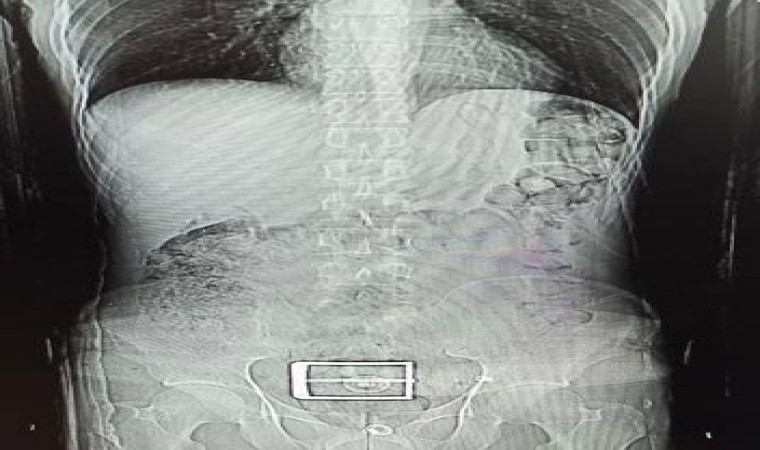

Edinilen bilgiye göre, Narkotik Suçlarla Mücadele ekiplerinin madde ticareti ve nakline yönelik yapılan çalışmalar sonucunda durumundan şüphelenilerek yakalanan ve uyuşturucu maddeleri yutarak nakletmeye çalışan İran uyruklu F.S. (30) yapılan iç beden muayeneleri sonucunda mide ve bağırsak kısmında 78 kapsül halinde 603,35 gr Afyon Sakızı ve 17 kapsül halinde 111,35 gr Metamfetamin maddeleri ele geçirildi.